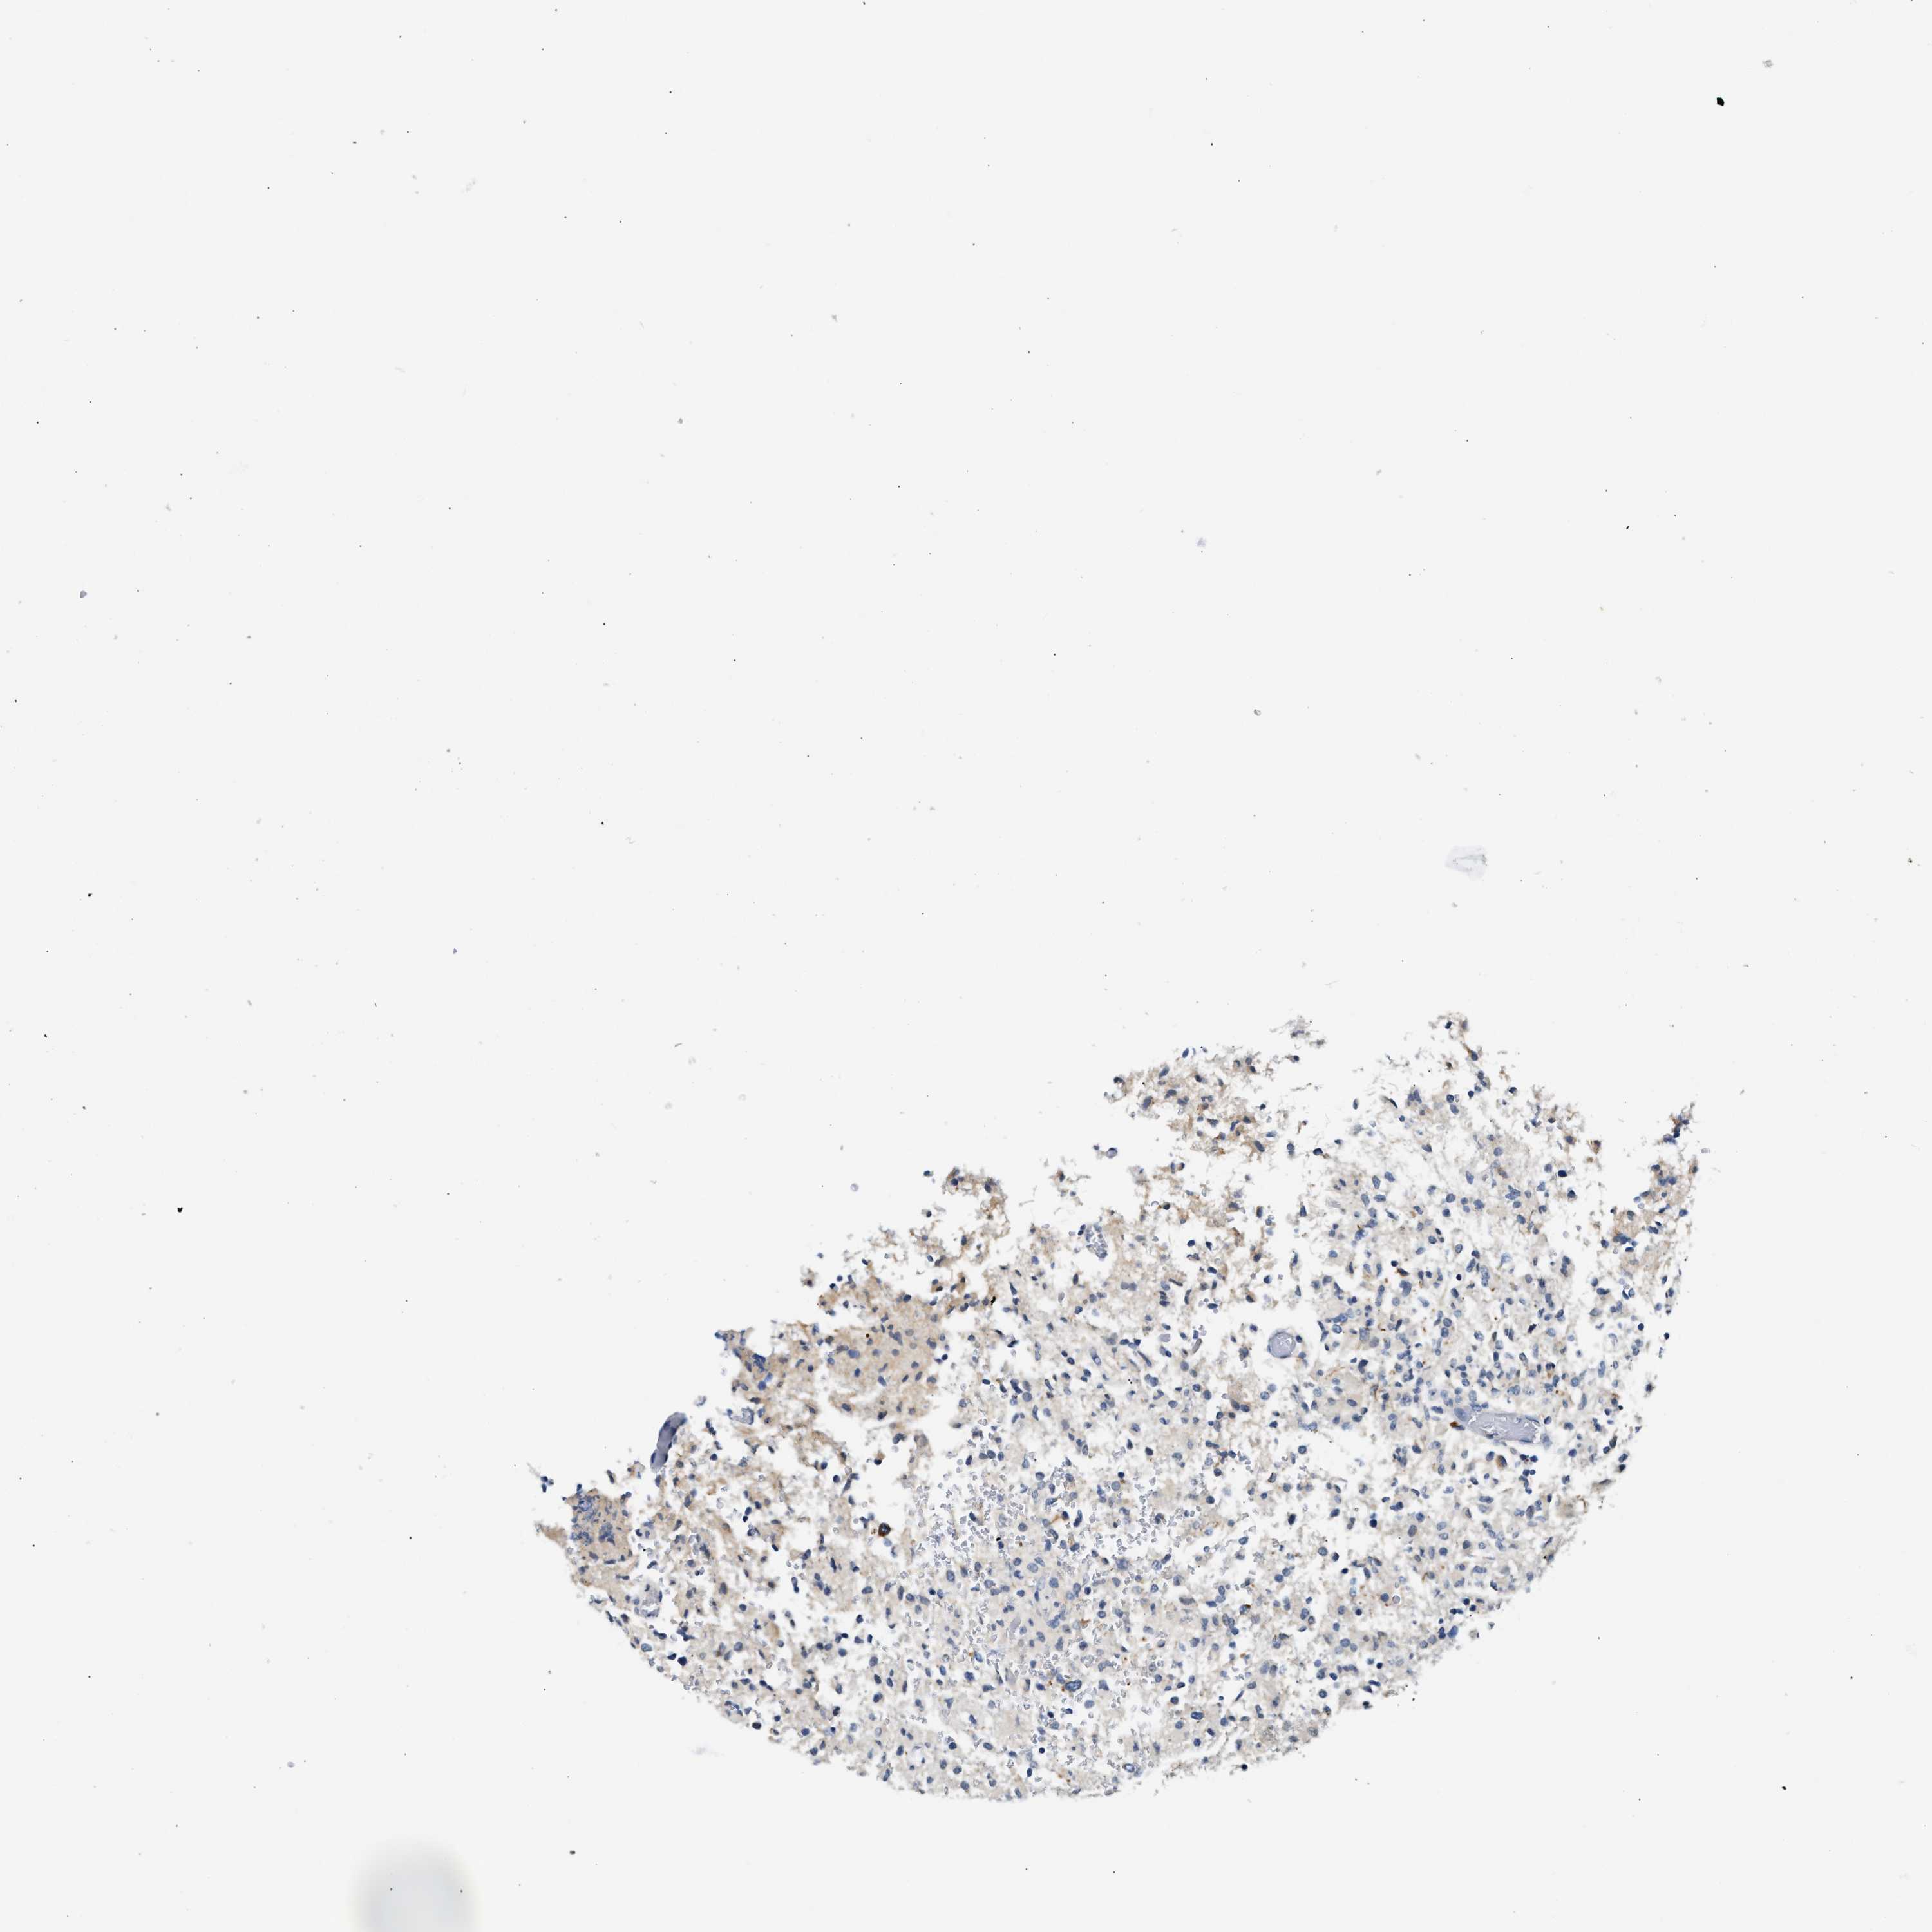

GLIOMA - Protein expressioni

A mouse-over function shows sample information and annotation data. Click on an image to view it in a full screen mode. Samples can be filtered based on level of antibody staining by selecting one or several of the following categories: high, medium, low and not detected. The assay and annotation is described here.

Note that samples used for immunohistochemistry by the Human Protein Atlas do not correspond to samples in the TCGA dataset.

Antibody stainingi

Antibody staining in the annotated cell types in the current human tissue is reported as not detected, low, medium, or high, based on conventional immunohistochemistry profiling in selected tissues. This score is based on the combination of the staining intensity and fraction of stained cells.

Each image is clickable and will lead to virtual microscopy that enables deeper exploration of all samples and also displays staining intensity scores, fraction scores and subcellular localization as well as patient and tissue information for each sample.

Antibody HPA020391

Staining

High

Medium

Low

Not detected

Intensity

Strong

Moderate

Weak

Negative

Quantity

>75%

75%-25%

<25%

None

Location

Nuclear

Cytoplasmic/membranous

Cytoplasmic/membranous,nuclear

Glioma, malignant, High grade

Glioma, malignant, Low grade